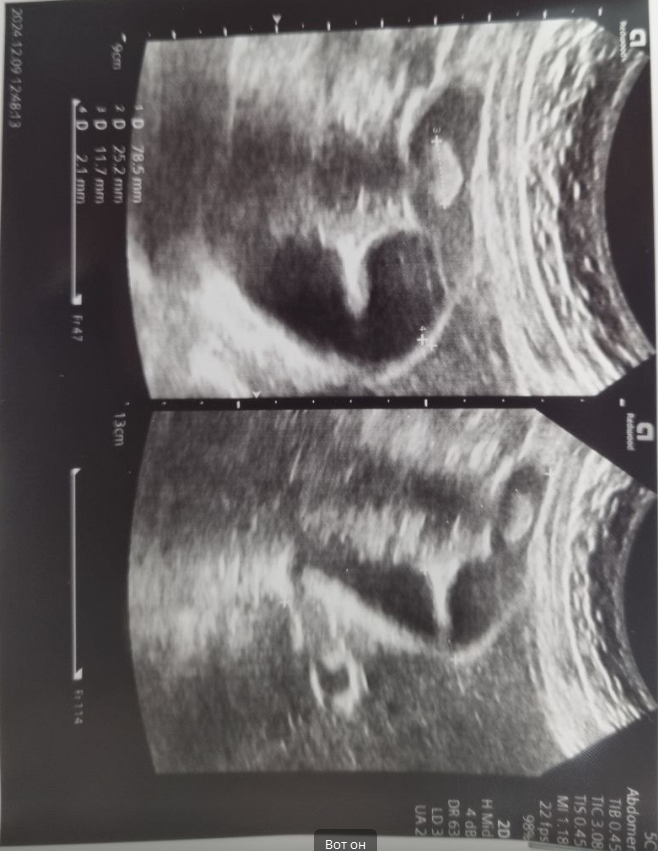

Нашли камень в желчном на узи. В 2021 - чисто. Пару дней назад на узи - плавающий 18мм. Кто-нибудь

Нашли камень в желчном на узи.

В 2021 - чисто.

Пару дней назад на узи - плавающий 18мм.

18 мм?

У меня тоже камень, 12мм.

У меня 18мм и охуеваю, пиздец.